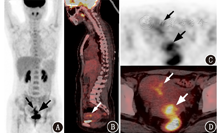

患者女,27岁,因"无明显诱因不规则阴道出血4个月"就诊,出血量少,色暗红,伴轻微下腹隐痛。超声提示宫腔内稍高回声,内膜息肉不排除;宫颈活组织检查病理提示宫颈高分化内膜样腺癌。实验室检查血常规、大小便常规、肝肾功能、凝血全套均正常,人附睾蛋白4(human epididymis protein 4, HE4)73(正常参考值范围:0~65) pmol/L,鳞状上皮细胞癌相关抗原、糖类抗原(carbohydrate antigen, CA)19-9、CA125、甲胎蛋白(alpha fetoprotein, AFP)、癌胚抗原(carcinoembryonic antigen, CEA)、神经元特异性烯醇化酶(neuron specific enolase, NSE)、绒毛膜促性腺激素(human chorionic gonadotropin, HCG)-β均正常。妇科检查发现宫颈"菜花"状肿瘤,短径约3 cm,宫体饱满。患者未婚未育,有性生活史,月经规律,无传染病史,否认手术史。MRI检查示宫颈内壁异常信号肿块,大小约29 mm×24 mm,T1加权成像(weighted imaging, WI)等信号,T2WI稍高信号,增强后呈均匀轻度强化;宫腔内见T2WI低信号结节,直径约16 mm,轻度强化。18F-脱氧葡萄糖(fluorodeoxyglucose, FDG)PET/CT(德国Siemens Biograph 16HR型)显像(图1)示宫颈稍低密度软组织肿块,FDG摄取明显增高,最大标准摄取值(maximum standardized uptake value, SUVmax)为8.1;宫腔低密度影,FDG代谢轻度增高,SUVmax为4.3。后行"子宫颈切除术+宫颈赘生物切除术",病理检查(图2)示宫颈、宫腔内膜腺体复杂性不典型增生,间质纤维组织增生,围绕腺体,考虑为非典型息肉样腺肌瘤(atypical polypoid adenomyoma, APA)。

PET/CT显像在APA中的应用国内外报道少见[7,8]。本病例中,PET/CT显像发现病灶FDG摄取明显增高,与国外报道相同;但本例病灶主要集中在宫颈。虽然部分子宫良性肿瘤可以摄取18F-FDG(如APA[2,7]、子宫肌瘤[8,9,10]等),但发生在宫颈的18F-FDG假阳性病例鲜有报道。根据本病例可知,对于宫颈18F-FDG高代谢的肿瘤性病灶,除考虑宫颈恶性病变外,还应考虑APA的可能性。值得注意的是,除了宫颈明显的APA病灶外,本病例子宫内膜也存在APA病灶,其在PET/CT显像上表现为子宫内膜轻度增厚,片状FDG摄取增高,SUVmax为4.3,鉴于患者为青年女性,需要与子宫内膜的生理性摄取相鉴别。目前APA摄取18F-FDG的机制并不清楚,Maeda等[7]发现APA中内膜腺体上皮细胞增殖活跃,18F-FDG摄取明显增高。APA是否同恶性肿瘤一样具有18F-FDG摄取程度与细胞增殖能力有关的特性,仍需要进一步研究。